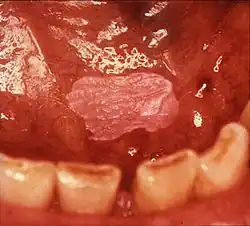

Non-homogeneous leukoplakia is a lesion of non-uniform appearance. The color may be predominantly white or a mixed white and red. The surface texture is irregular compared to homogeneous leukoplakia, and may be flat (papular), nodular or exophytic.[9][15] "Verrucous leukoplakia" (or "verruciform leukoplakia") is a descriptive term used for thick, white, papillary lesions. Verrucous leukoplakias are usually heavily keratinized and are often seen in elderly people. Some verrucous leukoplakias may have an exophytic growth pattern,[2] and some may slowly invade surrounding mucosa, when the term proliferative verrucous leukoplakia may be used. Non-homogeneous leukoplakias have a greater risk of cancerous changes than homogeneous leukoplakias.[9]

Erythroleukoplakia (also termed speckled leukoplakia, erythroleukoplasia or leukoerythroplasia) is a non-homogeneous lesion of mixed white (keratotic) and red (atrophic) color. Erythroplakia (erythroplasia) is an entirely red patch that cannot be attributed to any other cause. Erythroleukoplakia can therefore be considered a variant of either leukoplakia or erythroplakia since its appearance is midway between.[22] Erythroleukoplakia frequently occurs on the buccal mucosa in the commissural area (just inside the cheek at the corners of the mouth) as a mixed lesion of white nodular patches on an erythematous background,[22] although any part of the mouth may be affected. Erythroleukoplakia and erythroplakia have a higher risk of cancerous changes than homogeneous leukoplakia.[22]